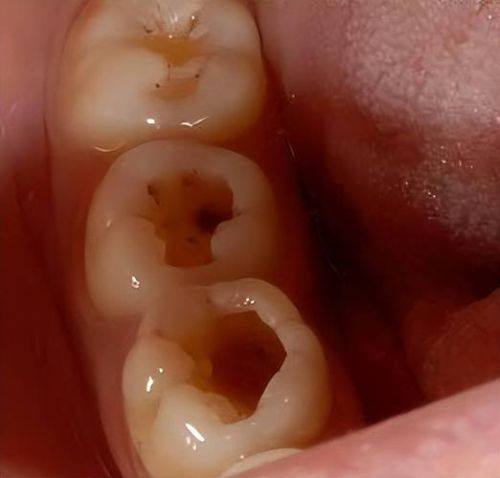

龋齿对口腔美观的影响是比较直观的。当牙齿出现龋坏时,牙齿表面会变得不平整,可能出现黑洞、缺损等情况。尤其是前牙发生龋齿,在与人交流、微笑时,这些龋坏的牙齿会暴露在外,影响个人形象。想象一下,当您自信地与人交谈,却因为一口有龋洞的牙齿而感到尴尬,这是多么影响心情的事情。而且,龋齿还可能导致牙齿变色,原本洁白的牙齿变得灰暗、发黄,进一步破坏了整体的美观度。所以,龋齿的危害具体有哪些中,影响美观是不容忽视的一点。

龋齿容易造成食物嵌塞在牙齿里。龋洞就像一个个小陷阱,当我们进食时,食物残渣特别容易陷入其中。这些嵌塞的食物如果不及时清理,就会在口腔内发酵、滋生细菌。细菌的大量繁殖会引发一系列口腔问题,比如口臭。口臭不仅会影响自己的口气清新,还会在社交场合中给他人带来不好的感受。此外,细菌还会刺激牙龈,引发牙龈炎,导致牙龈红肿、出血。如果牙龈炎得不到及时治疗,还可能进一步发展为牙周炎,使牙齿周围的支持组织受到破坏,牙齿变得松动,咀嚼功能也会随之下降。所以,龋齿引发的食物嵌塞和口腔疾病也是龋齿的危害具体有哪些中的重要方面。

如果龋齿的症状没有得到有效控制,病情会逐渐加重。龋坏的细菌会继续向牙齿内部深入,引发牙髓炎。牙髓炎会导致剧烈的牙痛,那种疼痛常常让人坐立不安,重度影响生活质量。随着炎症的蔓延,还可能发展为牙周膜炎、根尖周炎。这些炎症会使牙齿周围的组织受到更重度的破坏,甚至可能引发间隙感染。当病情发展到重度程度时,还会形成颌面部的蜂窝织炎。颌面部蜂窝织炎是一种比较重度的感染性疾病,会导致面部肿胀、疼痛,甚至可能影响到呼吸和进食。由此可见,龋齿如果不及时治疗,炎症的进一步发展会带来多么重度的后果,这也是龋齿的危害具体有哪些中需要重点关注的。